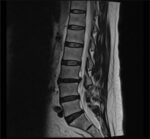

If you have an MRI, we review it directly and match it to your physical exam and X-ray findings. That helps us narrow down the most likely pain generator and avoid “treating the report.”

The best MRI review happens in the office

If you’re ready to move forward with care, the most accurate evaluation comes from an in-office exam. Dr. McClean reviews your MRI alongside static and motion X-rays taken in the clinic and a hands-on physical exam. That combination. Not the MRI alone. Is what produces an accurate diagnosis and a treatment plan.